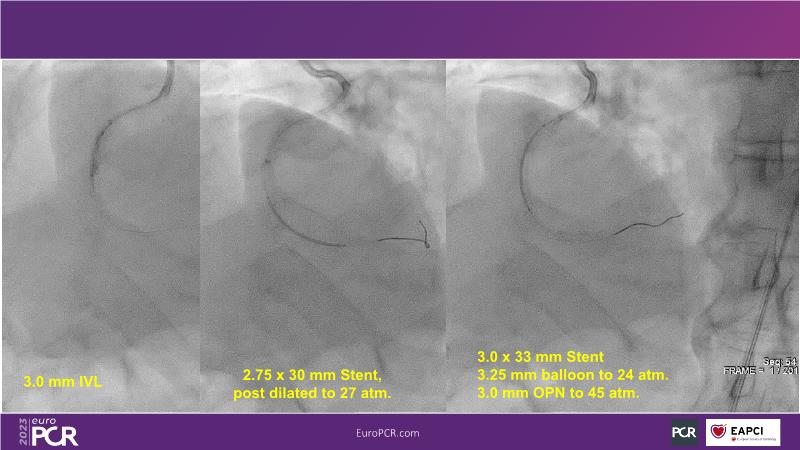

In this session, review the evolution in the use of IVL over the last few years, with a widening of the indications, observe that OCT can underestimate the number and depth of calcium fractured induced by IVL, or see that the technique is safe and effective in high-risk patients, including ACS patients, as demonstrated in real-world registries, among others!

- To understand how intravascular lithotripsy (IVL) in clinical practice has evolved over the last five years

- To evaluate the effects of IVL in different patterns of calcific coronary disease